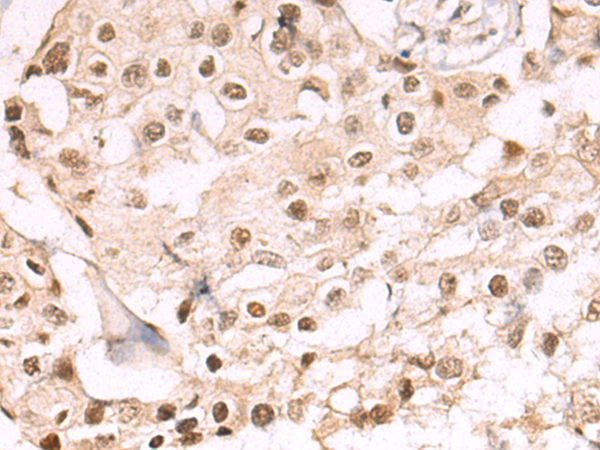

分类: 科研抗体货号: P10645别名: AM2; dJ579N16.4应用: IHC反应种属: Human, Mouse, Rat